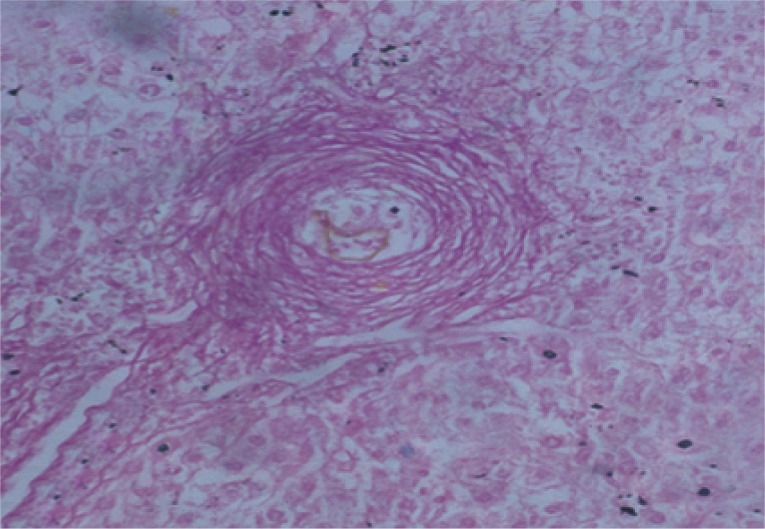

The mean granuloma count in the treated groups with BMSCs and BMSCs-HGF revealed a marked reduction accompanied by an obvious reduction in the mean granuloma number and diameter (Table 1; Figs. 2, 3).

Morphometric studies using Sirius red staining showed significant decreases in the fibrous tissue in BMSCs and BMSCs-HGF-treated groups compared to the infected control group (Figs. 6,7,8,9,10,11,12,13,14,15).

After treatment with BMSCs alone or in combination with HGF, there was an improvement in the histopathological picture of the liver which included diminution in the number and diameter of granulomas and reduction in the fibrotic content. Similar to the present findings, Abdel Aziz et al. [13] focused on the antifibrotic effect of mesenchymal stem cells (MSCs) on the liver of S. mansoni-infected mice. In their model, once granulomas were formed around the S. mansoni ova, the rate of spontaneous change of the collagen content of the granuloma was low, thereby providing a relatively stable in vivo model for analyzing collagen turnover. The histopathological examination of the liver of the S. mansoni-infected mice showed characteristic granulomas, which were cellular and contained thick collagen bands. After MSCs infusion, the granulomas decreased in size and number and became less cellular, although the concentric fibrous bands were still discernible.